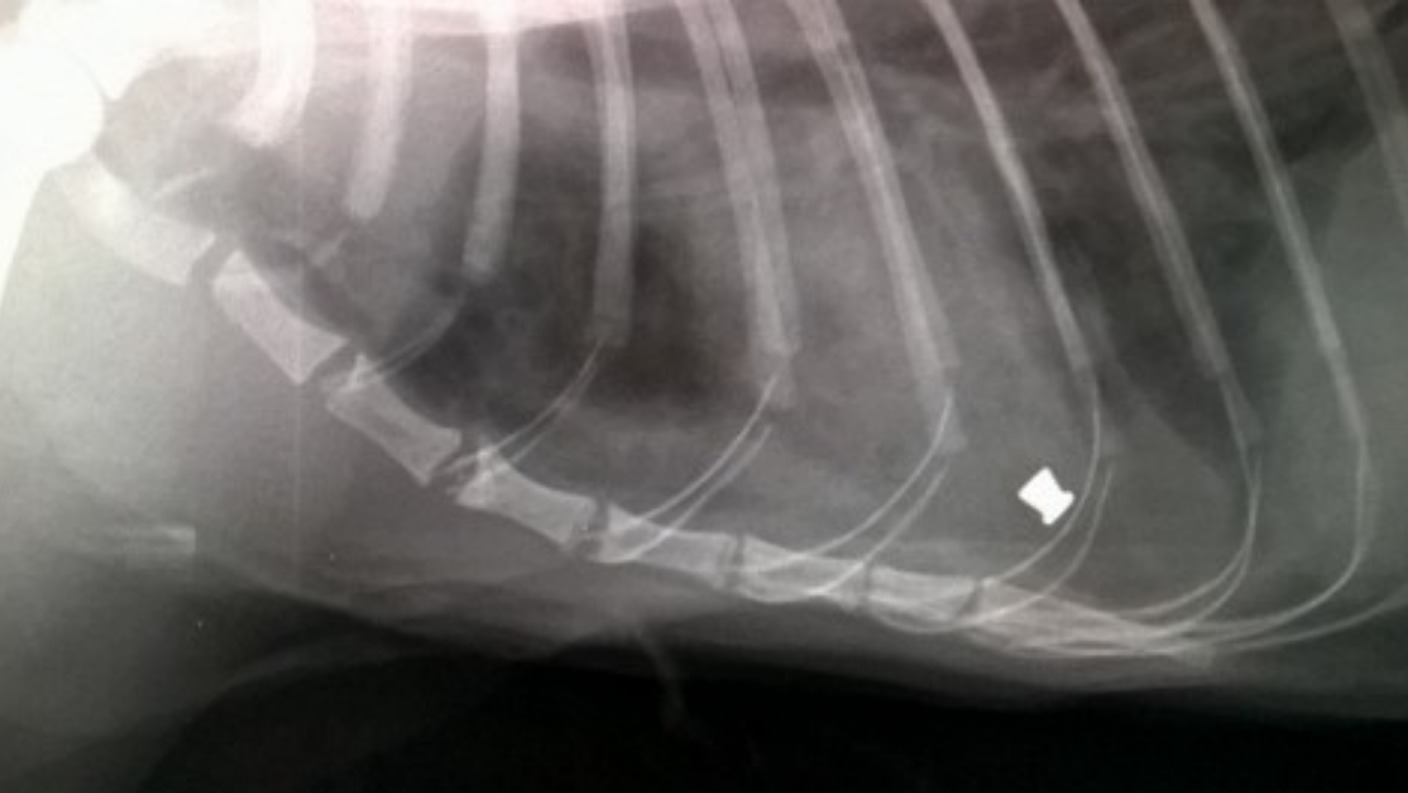

Cat that was shot in the face with a pellet gun is doing much better

Cat that was shot in the face with a pellet gun is doing much better Will A Pellet Gun Hurt A Cat Yes, a pellet gun has the potential to kill a cat. Unfortunately, many cats are victims of gunshot injuries after being shot with a firearm or air gun. Your closeness, too, matters a great deal. Bb guns are capable of causing serious injury or even death to cats due. Cats protection has been campaigning for air gun licensing in england. Will A Pellet Gun Hurt A Cat.